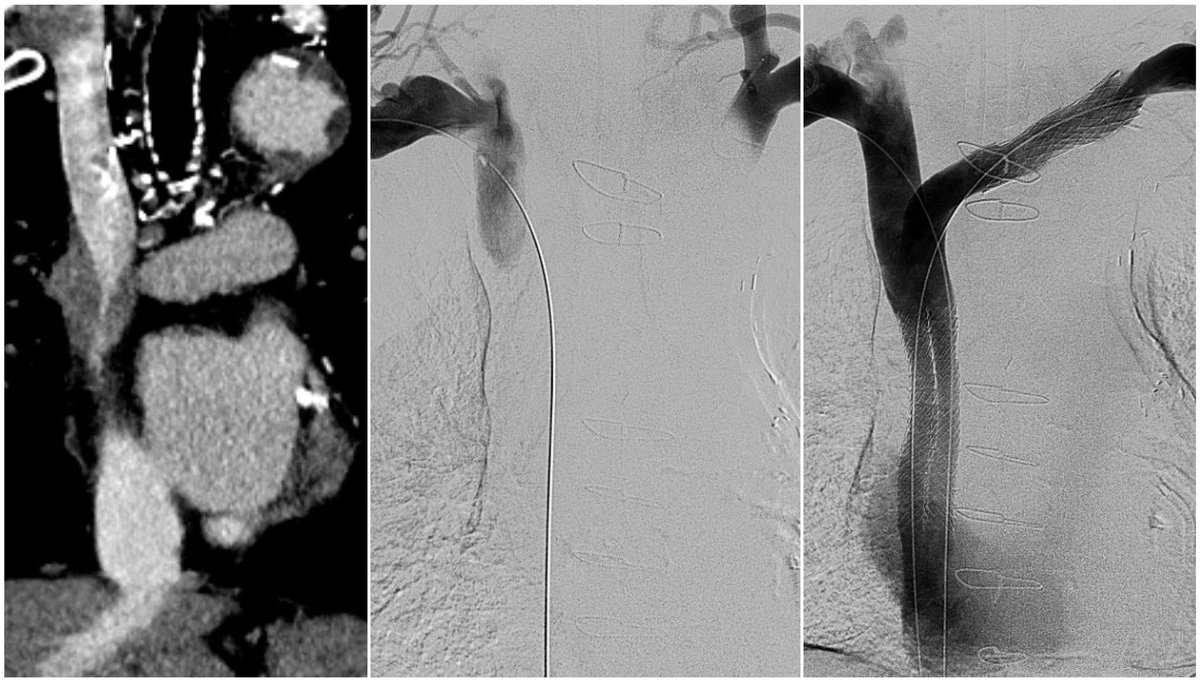

SIR published a new position statement offering recommendations on the management of chronic iliofemoral venous obstruction with endovascular placement of metallic stents. Access the statement on jvir.org to review suggestions and analysis. fal.cn/3Apcy